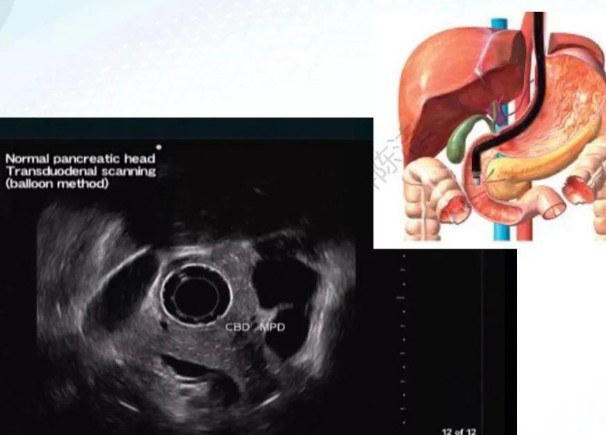

超声内镜,英文名Endoscopic Ultrasound,简称EUS,是将内镜和超声相结合的消化道检查技术。该技术将微型高频超声探头安置在内镜顶端,当内镜插入消化道后,在内镜直接观察消化道病变的同时,利用内镜下的超声行实时扫描消化道及周围结构。

超声内镜充分发挥内镜和超声双重优势,从而获得更清晰、全面的超声图像。超声内镜可以获得胃肠道的层次结构的组织学特征,及周围邻近脏器的超声图像,对消化道病变性质进行鉴别诊断,判断其侵袭深度和范围,鉴别病变的良恶性。

超声内镜与胆胰疾病

超声内镜有较高的敏感性,诊断胆胰疾病的准确率>95%,相比于CT、MRI、MRCP有独特优势,特别适合小病变的发现,如胰腺、壶腹部<1cm、胆总管<0.5mm的病变。

图片

超声内镜由于紧贴病变部位,在对胆总管、壶腹部小占位病变性质的了解、肿瘤浸润深度的判断、病变与周围脏器的关系等方面表现出不可替代的优越性。